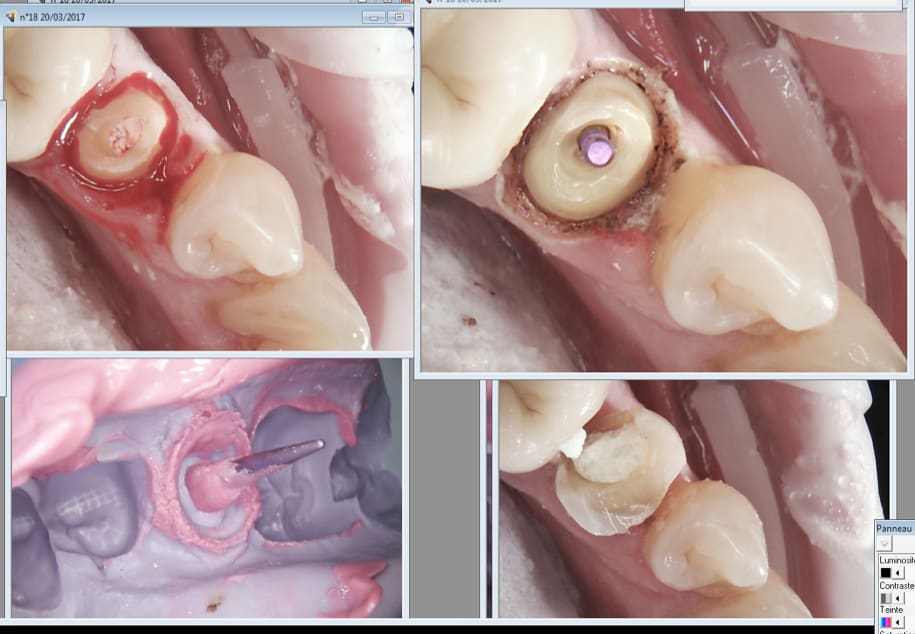

Tiens suite de mon Ic à 4 pattes empreinte prise le 9 03 et pose aujourd'hui. Aspect de la gencive encourageant après le coup de laser.

Capture d écran 2017 03 20 13.14 - Eugenol

J'ai d'ailleurs récidivé pour l'empreinte de la couronne. -)

Capture d écran 2017 03 20 13.19 - Eugenol